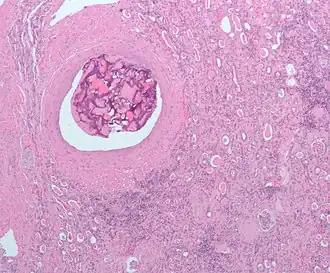

Эмболиза́ция (эмболотерапия[1]) — малоинвазивная рентгенохирургическая эндоваскулярная процедура. Состоит в избирательной окклюзии (закупорке) кровеносных сосудов специально введёнными эмболами. Выполняется интервенционным радиологом (рентгенохирургом).

Эмболизация — это малоинвазивная внутрисосудистая процедура, альтернативная традиционному хирургическому вмешательству[* 4]. Лечение направлено на предотвращение кровоснабжения определенных органов, тканей, структур организма, что помогает уменьшить размеры опухоли или блокировать аневризму.